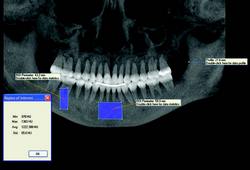

CBCT imaging is the ideal radiological modality for implantology due to the high quality of the produced images, software capabilities, and lower doses of radiation exposure. Two of the hottest topics regarding CBCT and implantology are virtual surgery planning and surgical guides. A virtual surgery can be performed with special software applications that enable dentists to evaluate the quality of bone through density shading and dimensions of bone can be recorded accurately with 1:1 measurement tools. It identifies common internal anatomy needed to evaluate implant placement including the jaw boundaries, adjacent teeth, nasal fossa, mandibular canal, maxillary sinus, mental foramen, and incisive canal. It also detects pathology to be avoided for implant health. Therefore, before the surgery, the clinician can confirm the appropriate implant size, location and angulation, and that plan can be fed to a 3-D printer to produce a surgical guide or stent for use during the actual surgery.